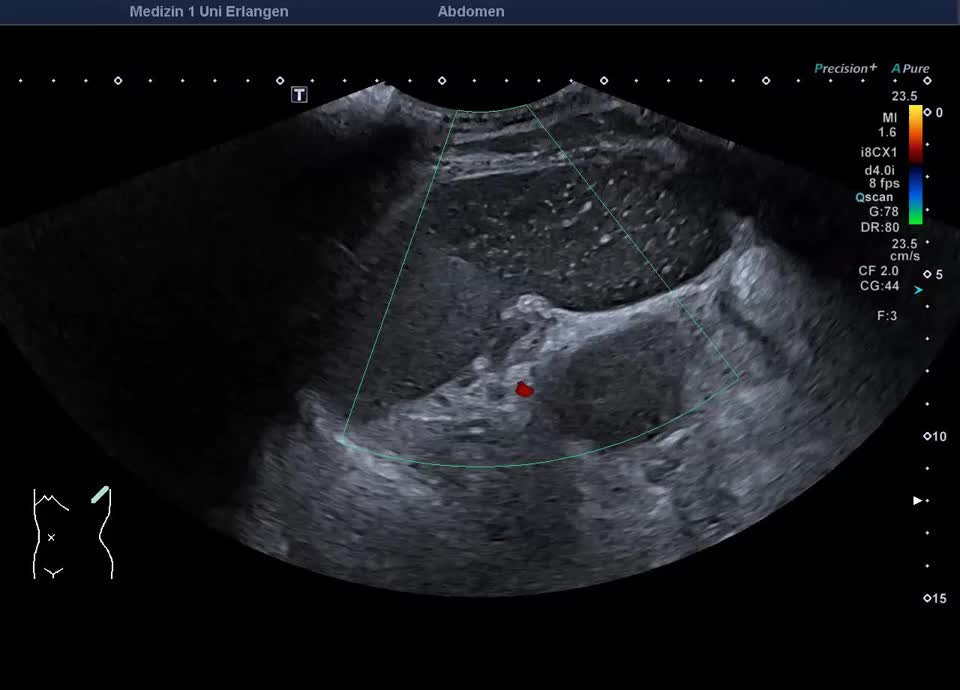

Splenic infarction

• Recent splenic infarction

• Recent splenic infarction (color Doppler)